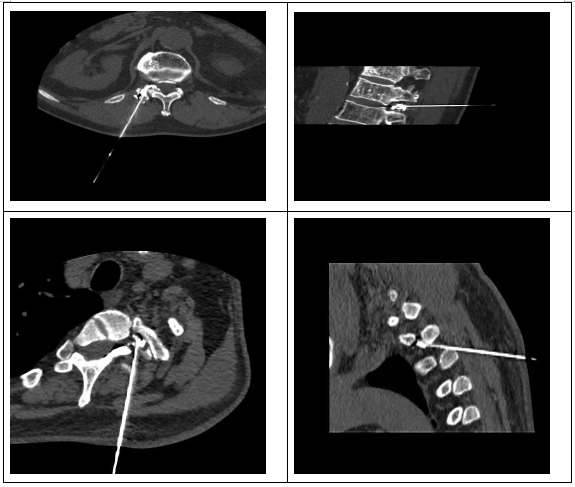

精准微创技术,直击疼痛根源。面对两位患者的病情,我院麻醉疼痛科、康复科、放射科迅速展开会诊,经详细评估后,决定采用CT引导下脊神经根脉冲射频调节联合神经根阻滞术为其治疗。放射科蒲鹏主任医师、泽旺初技师团队基于128排螺旋螺旋CT搭载的高分辨率动态三维成像技术,凭借毫米级精度构建穿刺通道三维模型,实现病灶靶区的立体导航定位规划最优穿刺路径,为临床制定个体化精准诊疗方案提供可视化决策支持,就像给医生装上了“透视眼”,确保治疗操作准确无误。在此基础上,通过脉冲射频调节,可有效调节神经功能,降低神经的敏感性;神经根阻滞术则能直接阻断疼痛信号的传导,双管齐下,从根源上解决疼痛问题。

整个手术过程在麻醉疼痛团队侯静主治医师、历叶林副主任医师、夏雷医师以及康复科李晓医师的配合下仅耗时1小时左右,创口微小,对患者身体的损伤极小。术后,两位患者疼痛症状便得到了明显缓解,脸上也终于露出了久违的笑容。